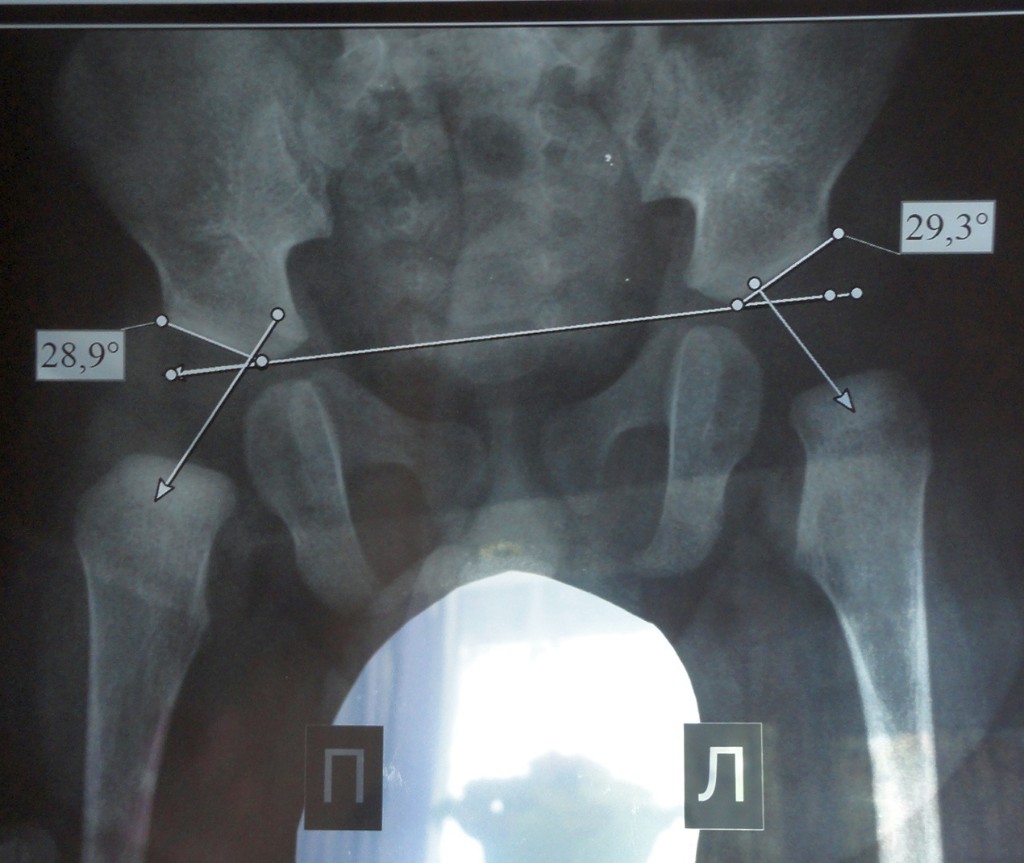

Рентген ТБС: Нормальные показатели

Раздел: Необычные решения